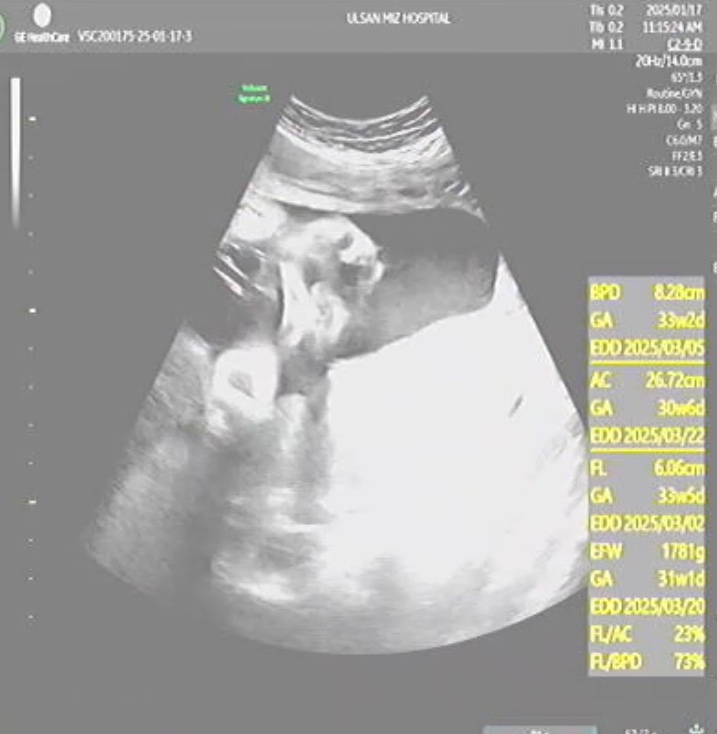

[임신36주] 작은아기, 배뭉침 잦음, 병원에 가야되는 배뭉침(자궁수축) 기준?

35주에 막달검사를 하고 매주 병원 진료를 간다. 태동검사 20분정도 하기때문에 시간 여유를 두고 가는게 ...